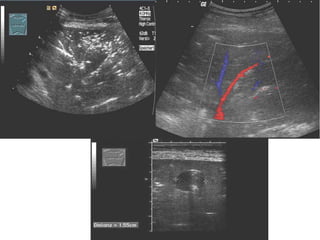

Tissue pattern representative of Alveolar

Consolidation

Presence of hyperechoic punctiform

imagesrepresentative of air bronchograms

Pleural

effusion

Lower lobe

Tissue pattern representativeof Alveolar Consolidation Presence of hyperechoic punctiform imagesrepresentative of air bronchograms Pleural effusion Lower lobe